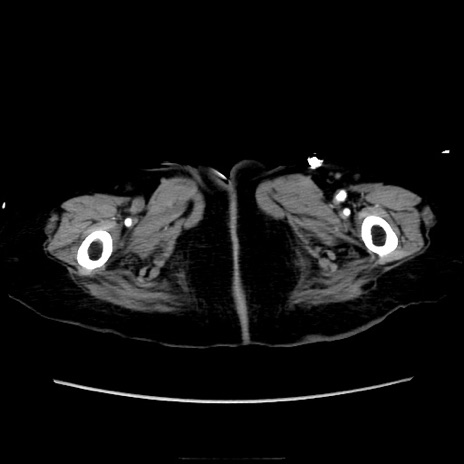

症例40(横断像)

【症例】90歳代女性

【主訴】腹痛・嘔吐

【現病歴】 食欲低下、嘔吐があり昨日他院受診。肺炎と診断され入院となる。入院後より腹部全体に圧痛あり。胃管留置され経過みていたが、症状持続するため、

当院転院となる。

【身体所見】腹部:中央に激痛あり、圧痛あり、反跳痛不明

【データ】WBC 17100、CRP 18.82